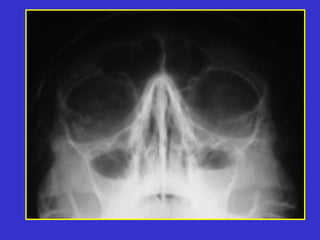

Este documento describe las diferentes proyecciones radiográficas utilizadas para examinar los senos paranasales, incluyendo las proyecciones básicas de Caldwell, Waters lateral y las proyecciones especiales como Hirtz y Waters mentonasal. También describe las diferentes estructuras anatómicas que componen el complejo ostiomeatal anterior y posterior de los senos paranasales.